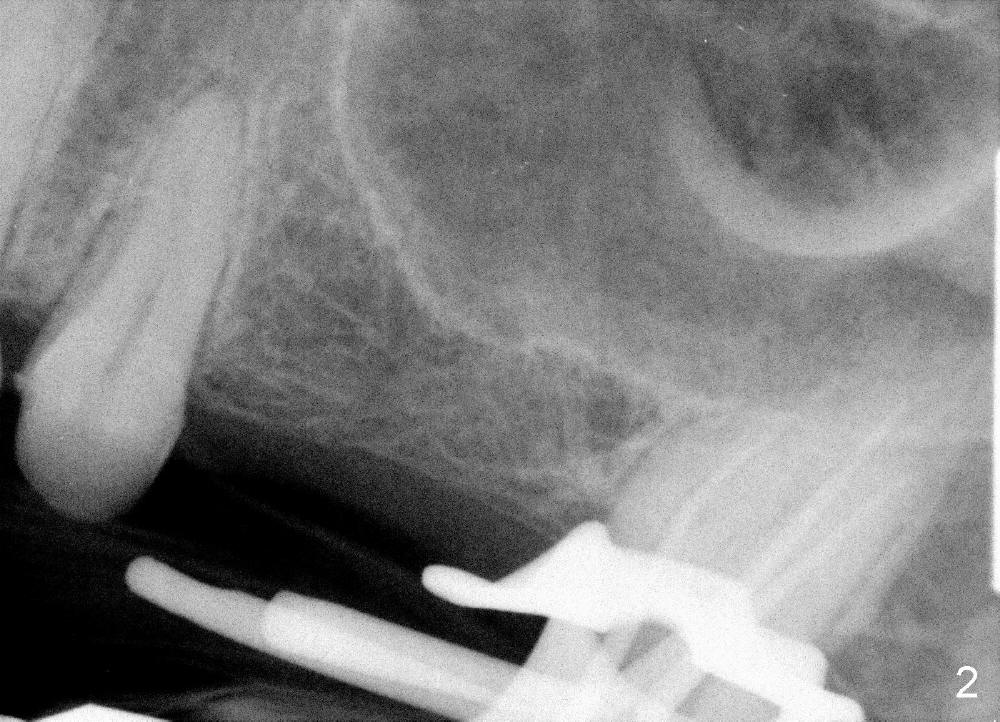

A 54-year-old lady has severe toothache in the upper left region. Exam reveals a posterior 4-unit bridge (Fig.1 B); one of the abutments (#15) needs root canal therapy (RCT, Fig.2). The bridge is temporarily recemented after RCT. Two implants are planned (4x14 mm and 5x11 mm at the sites of #13 and 14) with sinus lift/graft (Fig.3).